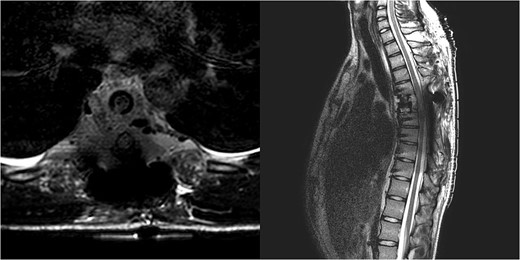

We decided to perform a revision total en bloc spondylectomy at Th6, along with resection of the Th8 pedicle and costovertebral joint, with a partial resection of the adjacent rib. Posterior spinal fixation from Th3 to Th10 was performed using radiolucent carbon screws, and the Th6 body was reconstructed using a radiolucent expandable cage (Figs 3 and 4). During the surgery, MEPs and SEPs were lost, with the patient waking up paraplegic (ASIA score B, VAS pain score 5). Immediate postoperative MRI showed no residual signs of thoracic spinal cord compression due to tumour or haemathoma (Fig. 5). The patient’s neurological status substantially improved the day after surgery, and thereafter, gradually improving over the next few days, allowing the patient to walk independently within 10 days (ASIA score D, VAS pain score 3). A multidisciplinary council decided against postoperative radiotherapy to avoid aggravating neurological symptoms by possibly causing additional damage to the myelopathic spinal cord. On the 11th postoperative day, the patient reported dyspnoea, and urgent CT angiography revealed peripheral pulmonary embolism, which was managed utilizing Deltaparine. Subsequent postoperative course was uneventful, leading to his discharge on the 15th postoperative day, ambulating independently using a walker. MRI follow-up was conducted 6 months postsurgery, followed by yearly checks. At the last follow-up, 2.5 years after the second surgery, there were no signs of tumour recurrence, and the patient exhibited no gait disturbance, back pain, or radiological signs of spinal instability (Fig. 6) (ASIA score E, VAS pain score 0).

Immediate postoperative MRI showing no residual signs of thoracic spinal cord compression.

Final follow-up X-Ray scan and MRI imaging showing no radiological signs of spinal instability or myelopathy.